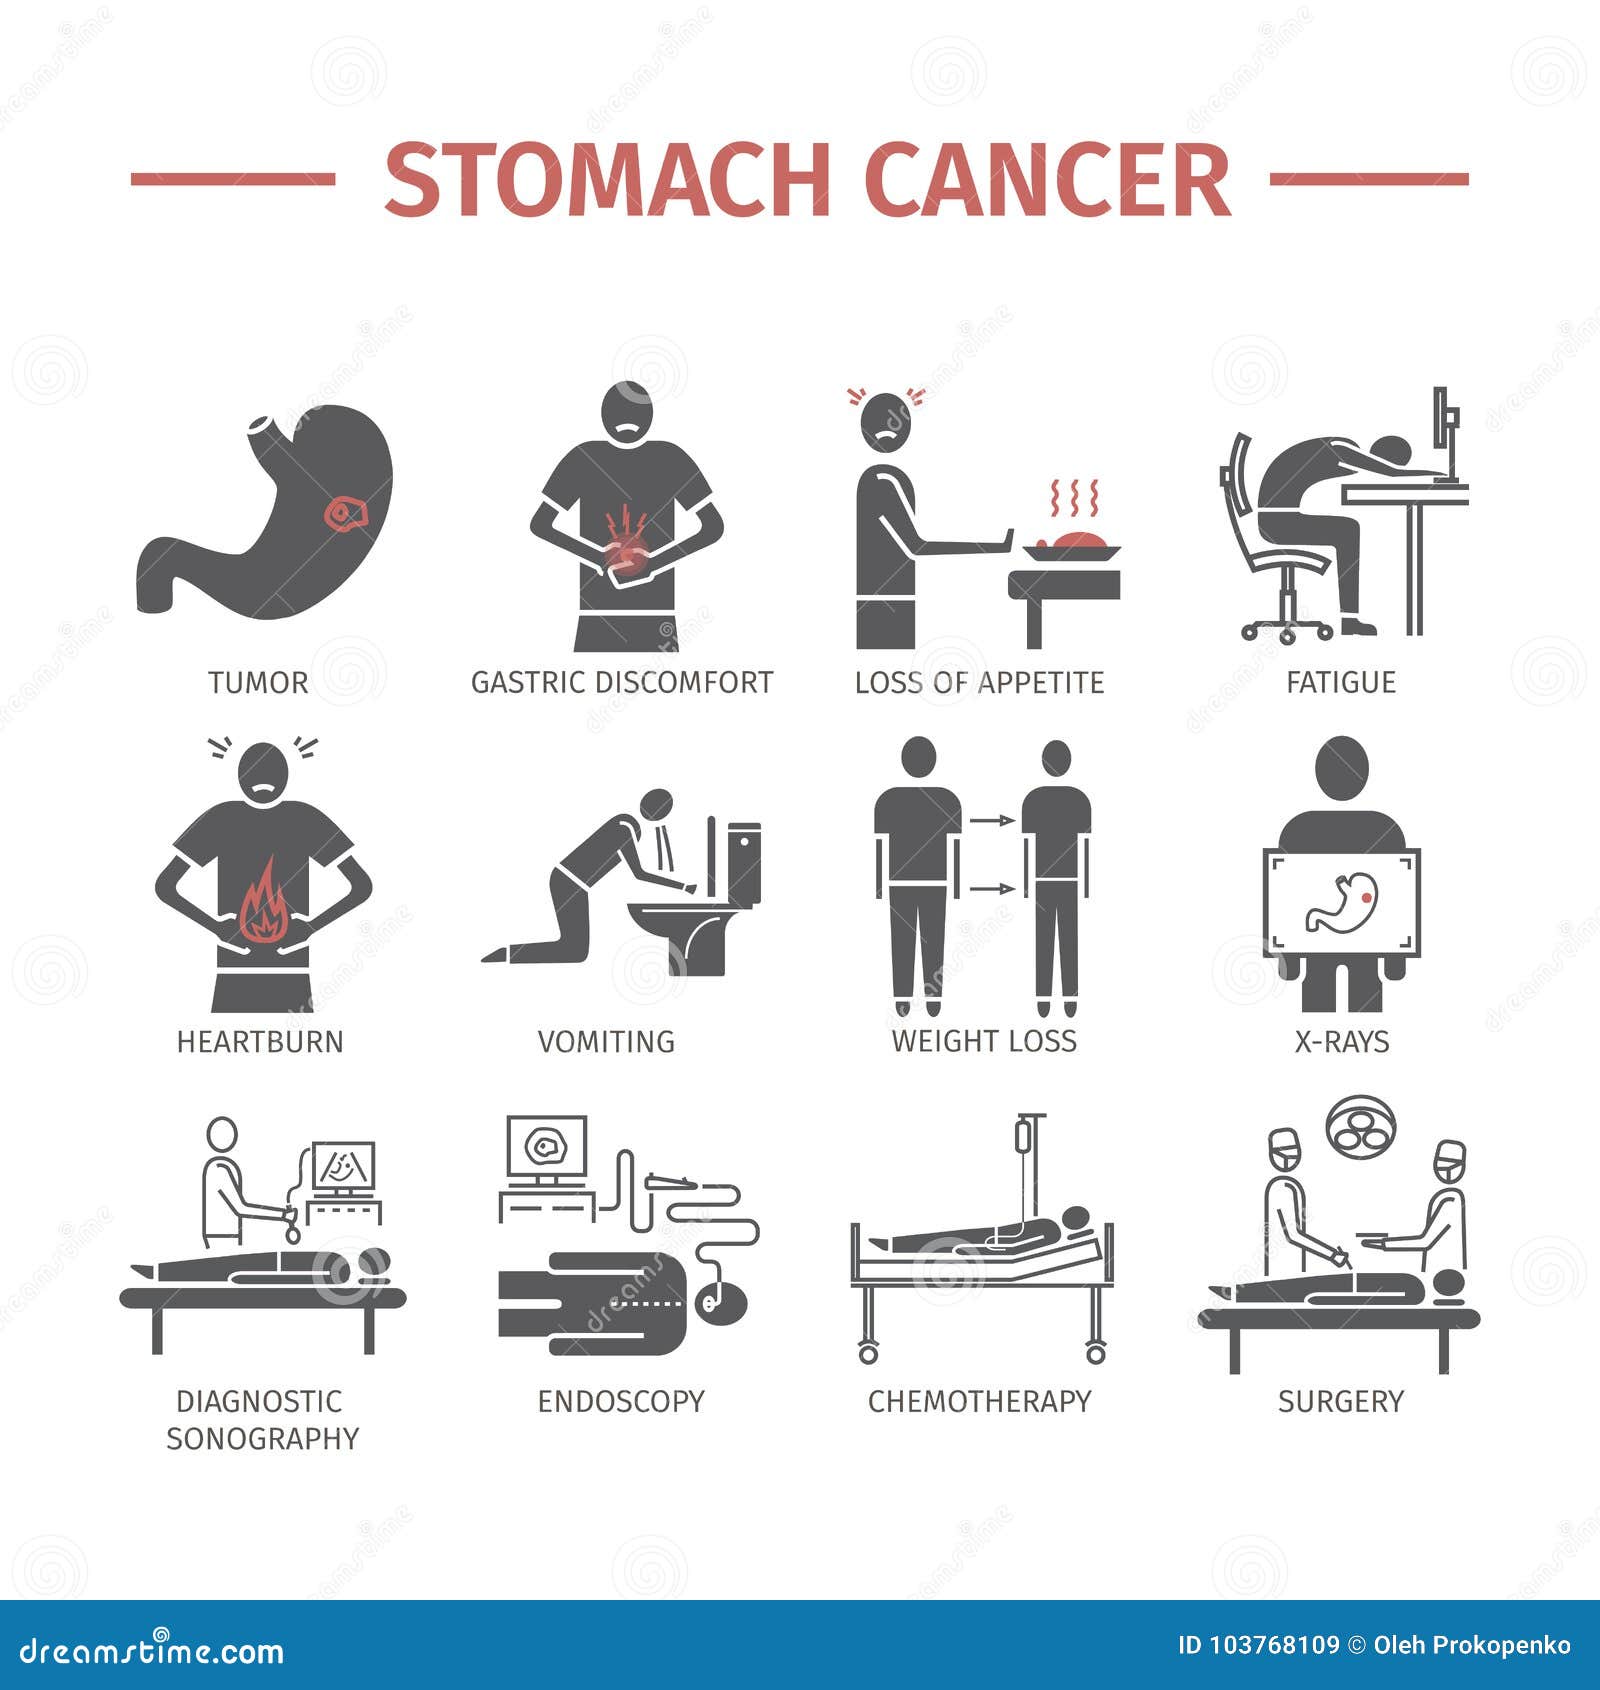

Stomach Cancer – Causes, Symptoms, Diagnosis and Treatment

Stomach Cancer | Symptoms, Causes, Stages, Treatment and Survival Rates

Stomach Cancer – Healthsoul

Stomach Cancer | Symptoms, Causes, Stages, Treatment and Survival Rates

Symptoms Of Stomach Cancer – Stomach Cancer Symptoms Causes Treatment …

Warning signs of stomach cancer

Symptoms Of Stomach Cancer – Stomach Cancer Symptoms Causes Treatment …

What Symptoms Do You Have If You Have Stomach Cancer : Quickly See If …

Stomach Cancer: Early and Late Symptoms > Niruja HealthTech

Stomach Cancer Icons. Symptoms and Diagnosis. Medical Infographics …

Stomach Cancer Icons. Symptoms and Diagnosis. Medical Infographics …